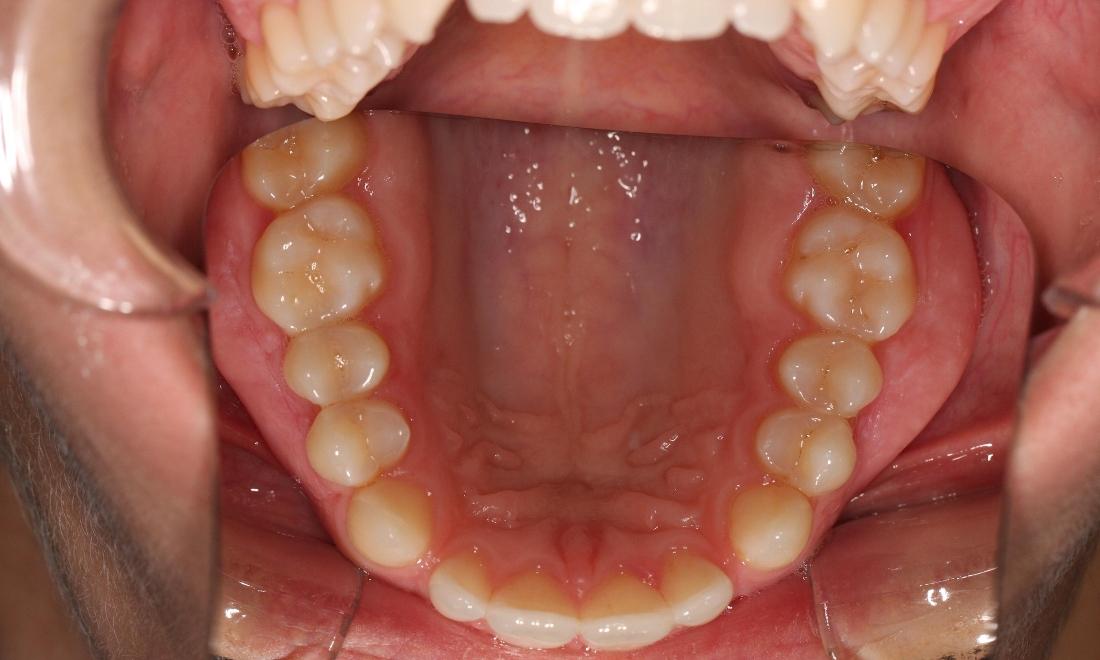

This young woman was self conscious about the crowding in her upper and lower teeth. After months of invisalign treatment, she is very satisfied with the result.